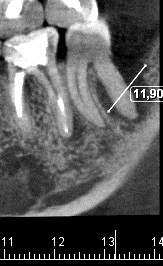

С понедельника держится высокая температура -- по вечерам 39,4 - 39,8. Кашель. У остальных членов семьи были похожие симптомы. Насколько я понимаю, это вирусная инфекция. На фоне высокой температуры дал о себе знать зуб, по поводу которого разные доктора разошлись во мнениях -- одни советуют удалять, другие попытаться вылечить. Планировал заняться этим после праздников, но процесс обострился раньше. Сейчас не знаю, что делать. Если не ошибаюсь, при простуде зубы удалять нежелательно? Но, и боль становится более интенсивной, сегодня ночью почти не спал. Болит в челюсти под проблемным зубом. Есть отек десны, появилась асимметрия лица. Посоветуйте что делать в этом случае.

Заранее благодарю.

Нажмите на изображение для увеличения

Название: 37.jpg

Просмотров: 82

Размер:	21.7 Кб

ID:	10749298

Вложение 10749298

едьте в скорую - вам окажут помощь. снимок берите с собой (ну или эту фотку) - если уже припухла щека - пора...